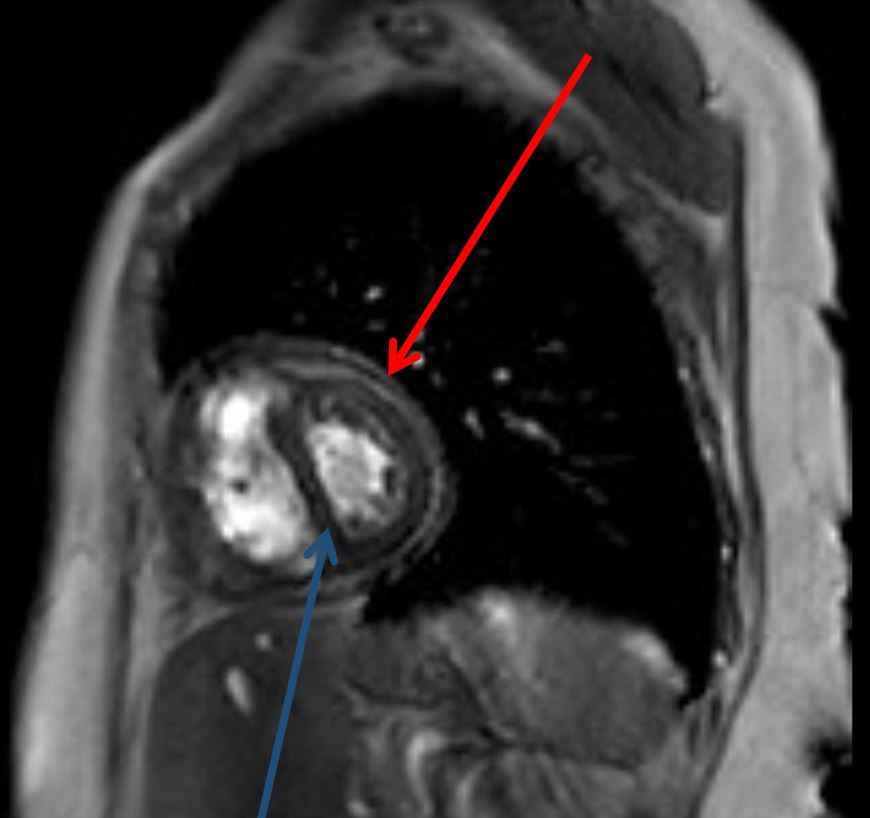

A 58-year old woman was admitted to the hospital for further evaluation of a recurrent right-sided, exudative pleural effusion requiring three prior therapeutic thoracenteses in the past month. She had no history of malignancy, radiation exposure, or recent infectious symptoms. Echocardiogram demonstrated a calcified pericardium with septal bowing into the left ventricle during inspiration. CT chest demonstrated a moderate right-sided pleural effusion with circumferential pericardial calcification. Cardiac MRI showed similar circumferential pericardial thickening with respirophasic variation of the interventricular septum consistent with constrictive physiology. Simultaneous right and left heart catheterization showed elevated and equal right and left ventricular diastolic pressure tracings as well as respirophasic discordance between the right and left ventricular systolic pressures.